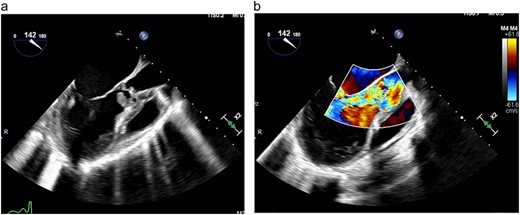

A transthoracic echocardiogram was thus performed and demonstrated normal left ventricular function, severe aortic regurgitation, a 2.33 x 1.89 cm vegetation on the aortic valve, moderate mitral regurgitation and severely dilated left atrium (Fig. 1). The cardiothoracic surgery team was consulted and the patient was taken to the operating room emergently for aortic valve replacement due to severely deteriorating hemodynamic status. Intraoperatively, she was found to have complete destruction of the right and left aortic valve leaflets with preservation of the non-coronary leaflet. The aortic annulus was also destroyed and detached from the left ventricle with a large vegetation under the right leaflet. The aortic root was completely debrided and the annulus was reconstructed with a bovine pericardial patch. Subsequently, an aortic root enlargement was performed and a 23 mm bovine pericardial tissue valve was implanted. Intraoperative gram stain showed rare polymorphonuclear leukocytes with no organisms and subsequent intraoperative tissue cultures showed no growth. Her postoperative course was unremarkable as she was rapidly weaned off vasopressors following surgery and extubated on postoperative Day 5. Due to her social circumstances, she remained inpatient and she was treated with a 6-week course of 2 g IV ceftriaxone and 1-week course of metronidazole for concomitant trichomonas infection. Following this she was discharged to home on hospital Day 42. During her hospitalization, a pelvic ultrasound was completed and did not demonstrate the evidence of pelvic inflammatory disease.

(a) TEE demonstrating large vegetation under aortic valve, (b) TEE demonstrating severe aortic regurgitation.